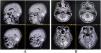

Case 2: Opalski syndromeA 35-year-old previously healthy man presented with sudden onset right hemiparesis, reduced sensation involving the left limbs, burning sensation over the right half of the face, unsteadiness of gait, and several episodes of fall, always to his right side, for the last three days. The family members initially thought the falls were due to extreme weakness associated with febrile illness. He also had complained of fever associated with headache, body ache, and a few episodes of vomiting for the last seven days. He had also recently noticed a peculiar change in the quality of his voice (hoarseness). There was no history of craniocervical trauma, nasal regurgitation, addiction, COVID-19, or vaccination in the recent past.

He was febrile (101 °F) and had tachycardia (100 bpm). Other vital parameters were unremarkable. Cognitive functions were normal. Cranial nerve examination revealed dysesthesia over the right half of the face and right-sided lower facial weakness (i.e., right-sided upper motor neuron type of facial palsy). Examination of the motor system revealed right-sided spastic hemiparesis (mMRC grade 4/5) with brisk deep tendon reflexes and a Babinski’s response on the same side. Sensory system examination showed decreased pain and temperature perception over the left half of his trunk and limbs. He also had truncal and gait ataxia. Clinical examination also disclosed the presence of right-sided incomplete/partial Horner’s syndrome (partial ptosis and miosis).

A complete blood cell count was suggestive of neutrophilic leukocytosis (15 080/µL with 81% neutrophils), raised erythrocyte sedimentation rate (58 mm in the first hour), and thrombocytopenia (96 000/µL). Renal, hepatic, and thyroid functions were normal. Serum electrolytes, fasting lipid profile, and blood glucose profile were within normal range, and so were the chest X-ray and echocardiography. Serologies for hepatitis B, C, HIV (1, 2), malaria, typhoid, Japanese encephalitis, and dengue were negative. Serologies for scrub typhus were positive (IgM-ELISA). A brain MRI with contrast revealed an altered intensity lesion hyper on T2-WI and T2-FLAIR sequences without diffusion restriction involving the lateral aspect of the right half of the medulla (Fig. 2). Both computerized tomography and magnetic resonance angiography of the brain did not reveal any abnormalities. CSF study revealed raised protein (60 mg/dL) with lymphocytic pleocytosis (15 cells; all lymphocytes) and low glucose (35 mg/dL). CSF oligoclonal bands were negative and tested for other relevant neuroviruses, anti-aquaporin 4-antibodies, and anti-myelin oligodendrocyte glycoprotein antibodies. Scrub typhus infection was further confirmed by testing for the organism using the PCR method in CSF.

Considering the diagnosis of an infective demyelinating event, he was put on oral doxycycline (200 mg/day) for two weeks. The condition of the patient improved after five days with antibiotics and physiotherapy. Neurological examination at discharge revealed only mild impairment of sensation over the left half of his body and facial pain over the right half of his face, for which he was prescribed pregabalin (75 mg/day) at bedtime. Follow-up three months after discharge revealed persistence of mild sensory abnormalities, but the patient was able to lead a fully independent life.

Case 2: the classical presentation of lateral medullary syndrome consists of crossed sensory deficits, specifically loss of pain and temperature sensation affecting trunk and extremities contralateral to the lesion and ipsilateral facial numbness.22 Other features of the syndrome include vertigo, nystagmus, hoarseness, dysphagia, ipsilateral cerebellar signs, and complete Horner’s syndrome.22 However, the clinical presentation is widely varied, depending on the sensorimotor, anatomical, and radiological involvement pattern, with classical features rarely observed.23,24 Our patient’s presentation differed from the classical description of Wallenberg in several aspects. Atypical features in our case, which questioned the diagnosis of the classical lateral medullary syndrome, were as follows: a) ipsilateral hemiparesis (Opalski syndrome); b) incomplete/partial Horner’s syndrome; and c) ipsilateral upper motor neuron type of facial palsy.

The eponym, Opalski syndrome, has been reserved only for those cases with ipsilateral hemiparesis with Babinski positivity and contralateral numbness.25 The cause of hemiparesis had been attributed to either caudal extension of the ischemic lesion to involve corticospinal fibers after the decussation or involvement of medullary penetrating arteries, which supply the post-decussation pyramidal fibers.25 These arteries are a branch of the vertebral artery, the most commonly involved artery in Wallenberg’s syndrome.26

The presence of incomplete or partial Horner’s syndrome (e.g., only partial ptosis and no miosis, anhidrosis) is due to the involvement of deeply located parts of the descending sympathetic tracts, which may be spared in a more dorsal medullary lesion leading to this differential involvement.22,27

The ipsilateral upper motor neuron type of facial palsy may be attributed to hypothetical looping supranuclear corticobulbar fibers, which descend in the contralateral ventromedial medulla and decussate at the level of the upper medulla and then ascend in the dorsolateral medulla to reach the facial nerve nucleus.27 Remarkably, though most frequently, this syndrome has been described following a vascular event, primary demyelinating events can also play the role of a culprit,28 and in this novel case, scrub typhus induced secondary demyelinating lesion over the lateral half of right medulla potentially gave rise to this syndrome.29 Clinicians should be aware of these atypical presentations of tsutsugamushi infections mimicking brainstem strokes.